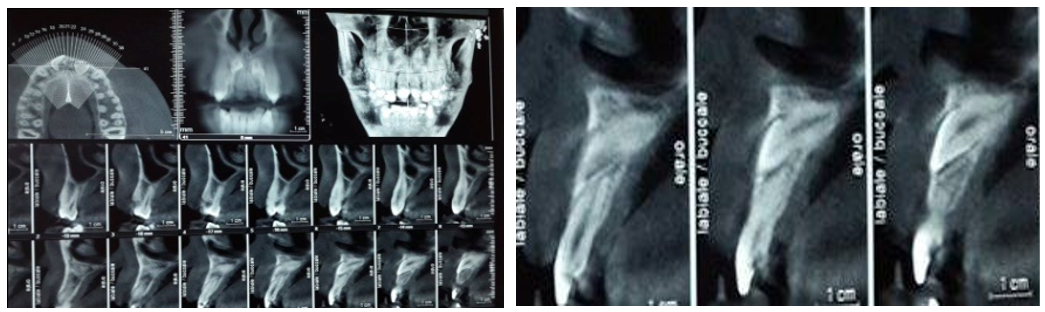

A panoramic radiograph (Figure 2) revealed the presence of two impacted teeth in the anterior region.

Figure 2 Panoramic radiograph.

To further investigate, a cone beam CT scan was performed, confirming the presence of retained teeth that were highly positioned near the nasal fossae, with an almost horizontal eruption axis, an apical curvature, and a morphology resembling that of typical central incisors. Sagittal slices revealed that the mesiodens had fully developed roots and an intact root canal system without significant calcifications (Figure 3).

Figure 3 a-b Cone beam shows the presence of two upper, nearly horizontal impacted teeth with an apical bend.